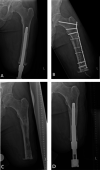

Background: Septic loosening and stem breakage due to metal fatigue is a rare but well-known cause of orthopaedic implant failure. This may also affect the components of the osseointegrated implant system for individuals with transfemoral amputation who subsequently undergo revision. Identifying risk factors is important to minimize the frequency of revision surgery after implant breakage.

Results: Thirty-four percent (20 of 58) of patients had revision surgery. In 12% (7 of 58) of patients, the reason for revision was due to intramedullary stem failures (six breakages, one septic loosening), and in 22% (13 of 58) of patients it was due to dual-cone adaptor failure (10 weak-point breakages and four distal taper breakages; one patient broke both the weak-point and the dual-cone adapter). Smaller median stem diameter (failure: 15 mm [interquartile range 1.3], nonfailure: 17 mm [IQR 2.0], difference of medians 2 mm; p < 0.01) and higher median number of infectious events (failure: 6 [IQR 11], nonfailure: 1 [IQR 3.0], difference of medians -5; p < 0.01) were associated with revision intramedullary stem surgery. No risk factors could be identified for broken dual-cone adapters.

Conclusion: Possible risk factors for system failure of this osteointegration implant include small stem diameter and high number of infectious events. We did not find factors associated with dual-cone adapter weak-point failure and distal taper failure, most likely because of the small sample size. When treating a person with a lower-limb amputation with a CoCrMb osseointegrated implant, we recommend avoiding a small stem diameter. Further research with longer follow-up is needed to study the success of revised patients.